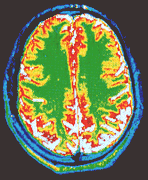

Brain scan

Of all the new applications of fractals, the most surprising comes from Dr Ed Bullmore and his team at the Institute of Psychiatry in London. They have been measuring the fractal nature of the human brain - and found links with depression and schizophrenia.

But the advent of medical scanning has breathed new life into Gall's idea. Scanning technology has been used to study the outer grey matter and the inner white matter of the brain. By measuring the fractal dimension ("jaggedness") of this boundary in dozens of patients. the team found that patients who suffer from manic depression have a more "jagged" grey-white matter boundary than normal people. In contrast. those with schizophrenia seemed to have particularly smooth boundaries.